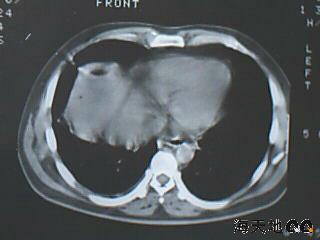

男 32y 外伤后一月余,现 t38.5,肝区隐痛。

右肝膈顶区液气平面.右膈肌增厚改变,病灶下部层面呈半月形延伸于肝表面.且于横结肠无明确密度切关系.

结合临床症状;考虑膈下脓肿.建议薄层矢状重建进一步证实.

鉴别;1,膈疝;2,间位结肠.

右隔肌与肝顶之间隙有长气液平,其下散在点状气体影,右侧腹膜局限增厚。考虑右膈下脓肿。

考虑右膈下脓肿。病灶不在肝内,位于肝外膈下;病灶下方的层面无结肠影与之相连。

右膈肌增厚,肝膈间见条状低密度影内可见积气影及宽大液平面,并未见与结肠相连。因此考虑膈下脓肿。